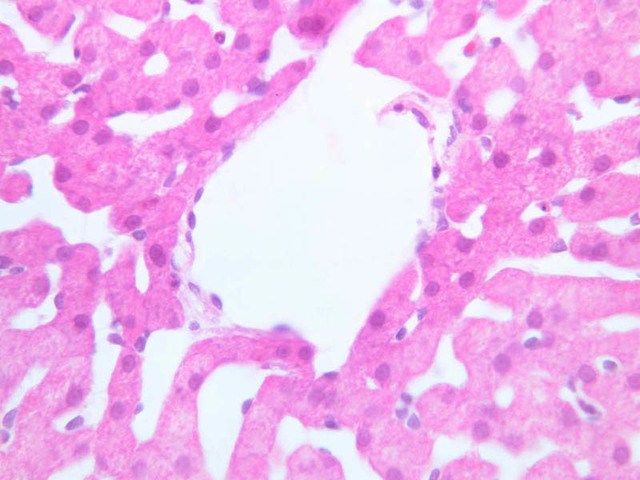

Examine the H&E-stained sections of liver (slides B-29 [10x, 20x, 40x-labeled] [2.5x-labeled, 10x, 20x, 40x] [10x-labeled, 20x, 40x-labeled] and B-30 [2.5x, 10x-labeled, 20x]). At low power, identify the connective tissue capsule (Glisson’s capsule), central veins and portal triads (portal canals). Note that the cells of the liver parenchyma (hepatocytes) appear as cords--more accurately, plates--of cells that radiate out from the central veins and partially enclose blood spaces known as hepatic sinusoids. Note that the plates of hepatocytes appear to branch and fuse and that, as a rule, they are only one or two cells thick. Do you see any binucleate hepatocytes?

Using the high dry objective, study the lining of the central vein and hepatic sinusoids (B-29). In some places the hepatocytes are exposed directly to the sinusoidal lumen, but, as a rule, there is a basal lamina which supports a discontinuous mosaic of endothelial cells and specialized phagocytic cells known as Kupffer cells. Find examples of Kupffer cells and endothelial cell nuclei. Note that in some places you may see a narrow space (the space of Disse) between hepatocytes and the basement membrane underlying endothelial and Kupffer cells. Using the oil immersion (100X) objective, look very carefully along the boundaries between adjacent hepatocytes to see if you can find a bile canaliculus--the most delicate portion of the bile duct system--the walls of which are formed by the plasma membranes of adjacent hepatocytes.